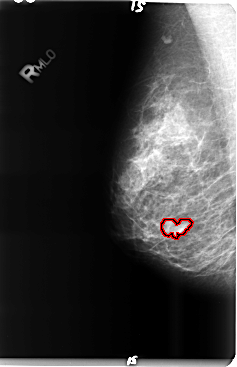

B_3491_1.RIGHT_MLO

RIGHT_MLO LINES 4768 PIXELS_PER_LINE 3080 BITS_PER_PIXEL 12 RESOLUTION 50 OVERLAY

FILE: B_3491_1.RIGHT_MLO.OVERLAY

TOTAL_ABNORMALITIES 1

ABNORMALITY 1

LESION_TYPE MASS SHAPE IRREGULAR MARGINS CIRCUMSCRIBED-ILL_DEFINED

ASSESSMENT 4

SUBTLETY 4

PATHOLOGY BENIGN

TOTAL_OUTLINES 1

BOUNDARY